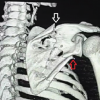

A 34-year-old male was assaulted with a knife which he tried to avoid with his left hand. In the process, he sustained a cut lacerated wound over his left wrist which was extending into the palm. There was profuse bleeding from the site of injury; however, there were no other injuries. The patient was rushed to the orthopedic casualty where the wound was washed and packed, and later, radiographs were ordered. The lateral view of the left wrist showed a complete dislocation of the pisiform bone (Fig. 1). The patient was taken up for surgery after a few hours. The surgical team comprised of a microvascular surgeon and an orthopedic surgeon. Surgery was performed under general anesthesia after applying a tourniquet. Wound exploration revealed that there was injury to both the ulnar vessels. The injury to the ulnar nerve was in zone 1 of the Guyon’s canal. The cut ends of both the ulnar nerve and ulnar artery were identified. There was an associated fracture dislocation of the pisiform bone; however, there was no injury to the FCU tendon (Fig. 2). After performing a thorough debridement of the wound, the pisiform bone was fixed back into its position using a 1.8 mm k wire. Later, repair of the ulnar nerve and artery was performed by the microvascular surgeon. Tension-less repair of both the ulnar artery and the nerve was done using 8-0 ethilon. Skin edges were sutured back and the wrist was immobilized in full volar flexion using a below elbow slab.